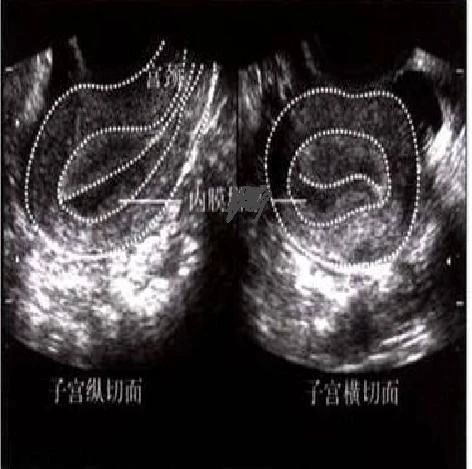

成功的妊娠必须具备两个条件:发育良好的胚胎和容受性良好的子宫内膜。子宫内膜就像孕育小生命的“土壤”,受精卵将像“种子”,“种子”能否存活生根发芽取决于“土壤”是否肥沃。而在这种关系中子宫内膜的容受性占了2/3的因素。评估子宫内膜容受性的指标涉及从影像学到组织学、超微结构、转录组学分析等诸多方面,其中临床应用历史最长、应用范围最广、对妊娠结局影响最为确切的仍属超声下子宫内膜厚度。

大部分相关研究中,定义使用自然周期排卵日或促排卵周期绒促性素( HCG) 扳机日内膜厚度小于7~9mm作为阈值。目前对于薄型子宫内膜厚度的阈值尚无临床共识,临床上多认为子宫内膜如不足7 mm即可影响正常妊娠,需临床干预,故将子宫内膜厚度≤7 mm定义为薄型子宫内膜;而将子宫内膜厚度不足5 mm者很难怀孕,是重度薄型子宫内膜的诊断标准。